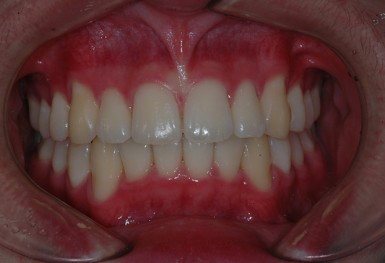

심한 덧니